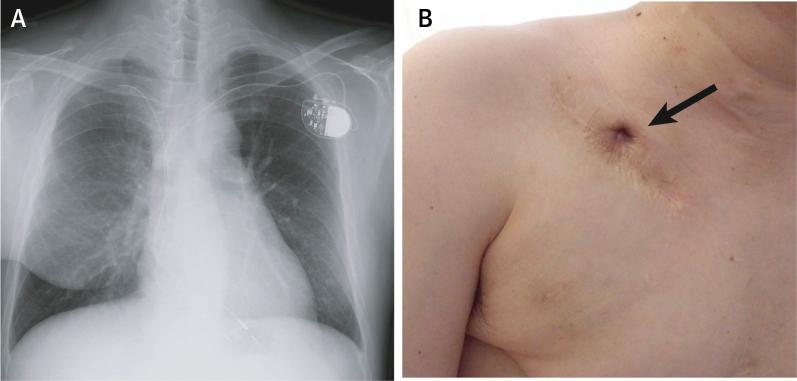

This report presents a new hybrid lead extraction technique combined with transatrial laser lead extraction and surgical removal of calcified lesions in a 50-year-old man with superior vena cava syndrome and bilateral subclavian vein occlusion caused by an abandoned lead, which had been infected for 11 years. ().

本报告介绍了一种新的混合式导线拔除技术,该技术结合经心房激光导线拔除术和手术切除钙化病变,应用于一名50岁男性患者,该患者因废弃导线感染11年,导致上腔静脉综合征和双侧锁骨下静脉闭塞。 ()